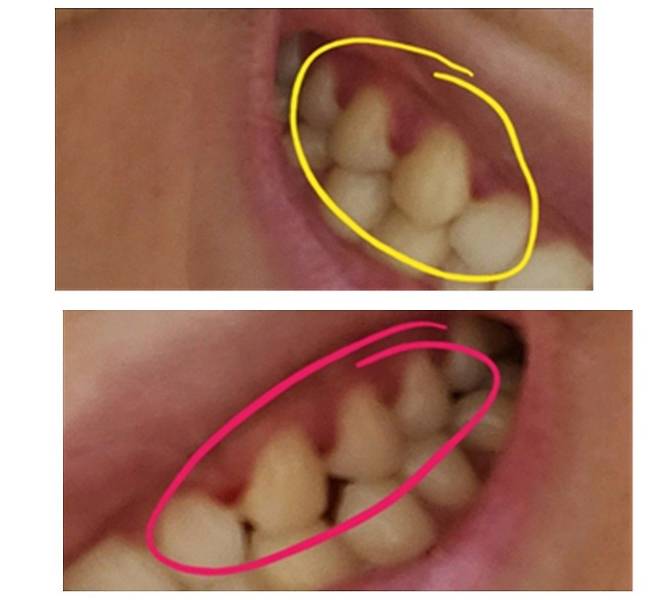

협회에 따르면 실제로 구입한 셀프 치아 장치로 인해 치아나 잇몸 손상, 부정 교합, 턱관절 장애 유발, 파손 또는 파절로 인한 기도 흡입 등 다양한 부작용 유발 사례들을 쉽게 찾아볼 수 있다.

대한치과교정학회도 “비전문가에 의한 셀프 교정 장치는 치아의 파절, 치아 괴사, 치관 파절, 치근 파절, 치아 발거, 잇몸 및 연조직의 외상과 궤양, 치조골의 상실, 보철물의 탈락 등 다양한 부작용이 발생할 수 있는 것으로 보고돼 있다”며 “치과의사에 의한 진단 및 치료 계획의 부재와 더불어 교정 진행 과정에서 유발되는 관찰과 치료 계획 변경도 불가해 소비자 피해를 최소화할 수 있는 최후의 기회마저 박탈될 수 있다”고 우려했다.